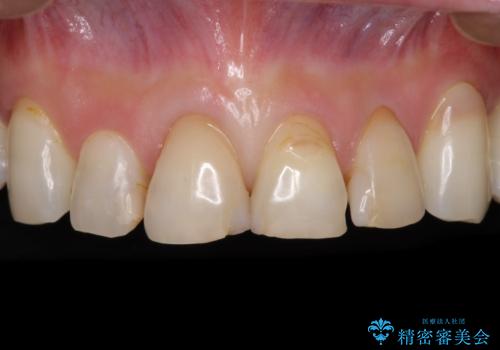

- 前歯の虫歯や治療跡が気になるとのことで来院された患者様です。

以前矯正治療をされ、その時には歯列が整ったので満足されたそうですが、若干の後戻りにより隙間ができ、矯正治療前に治療していた虫歯の跡が気になったため、オールセラミックによる審美治療を希望されました。

目立つ範囲である前歯4歯をオールセラミッククラウンにて補綴することとしました。